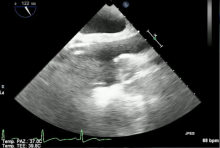

The right axillary artery and right femoral vein are identified by means of ultrasound and marked on the skin. Surgical exposure and isolation of the right axillary artery is performed through a limited skin incision 3 cm in length. A purse string suture (4-0 polypropylene) is placed, and heparin is administered (target activated clotting time >450 s). The right axillary artery is punctured and a guide wire is introduced under echocardiographic monitoring. Progressive dilatation is performed and cannulation is achieved with a straight wire-reinforced cannula over the guidewire. Next, sonographically-assisted percutaneous puncture of the femoral vein is performed. A long guide wire is guided well into the superior vena cava using echocardiography. Progressive dilatation is performed. The right atrium is cannulated under echocardiographic guidance with a long two-stage wire-reinforced venous cannula placed over the guidewire. The cephalad opening of the cannula must enter the superior vena cava for adequate venous drainage.